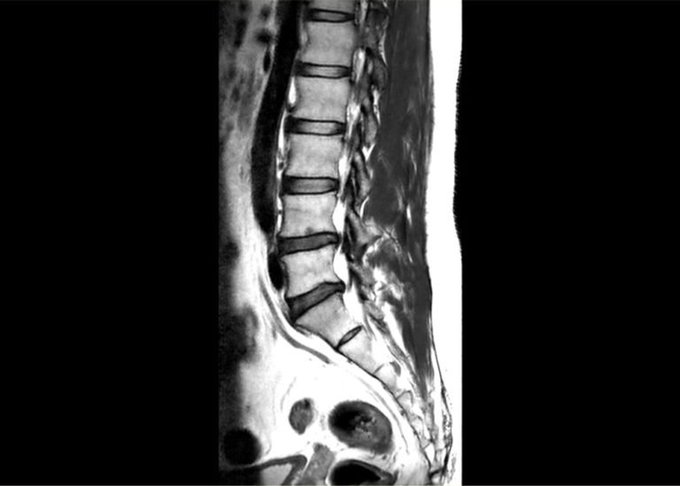

Thoát vị đĩa đệm

Thoát vị đĩa đệm lưng xảy ra khi nhân keo của đĩa đệm bị đẩy ra ngoài và chèn ép lên dây thần kinh, tủy sống. Hậu quả là gây đau, tê và yếu. Nguyên nhân: Chấn thương hoặc đĩa đệm bị mòn.